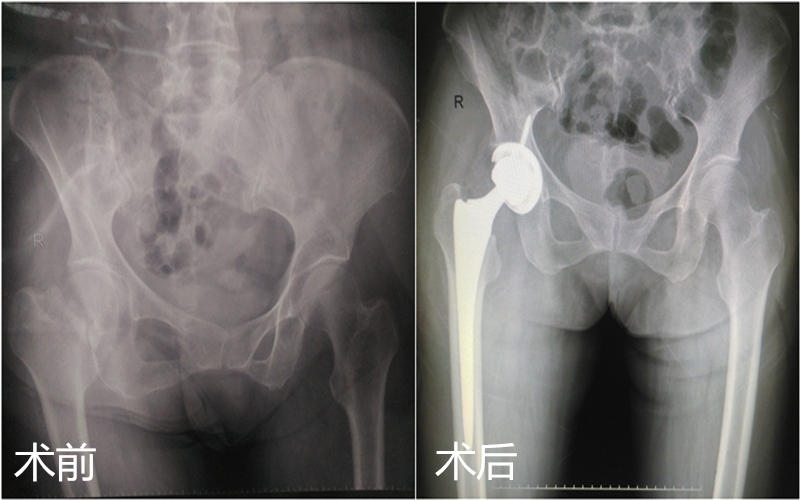

2018年金秋伊始,年近70岁史阿姨,清晨像往常一样到广场锻炼身体,并且要为马上进行的广场舞决赛做准备工作,但一次不小心的摔倒却让她错过了比赛,家人立即带老人到我院检查,却得知:这并不是简单的皮外伤,X线片清晰的显示史阿姨的右侧股骨颈骨折。我院骨一科接诊医生立即为患者办理了住院手续及术前检查,并拟定了手术方案,因史阿姨的右侧股骨颈骨折属于头下型骨折,Garden IV 型属于不稳的型骨折,如果选择固定,术后股骨头缺血性坏死的几率较高,且术后不能早期负重,建议行人工全髋关节置换术,迅速与麻醉科、心内科多学科联合评估手术风险,排除了其他手术禁忌后,于伤后48h内就为史阿姨做了手术,术中应用小切口、保护梨状肌、控制出血、修复外旋肌群及关节囊及不放置引流管等方法,术后指导踝泵练习、应用抗凝药物等为快速康复奠定了基础。并在术后24h帮助史阿姨重新站起负重,术后48h就可以在助行器辅助下行走,术后第四天就办理了出院。出院前除了告知常规的术后注意事项,另外提醒史阿姨别忘了广场舞的动作,因为3个月后又可以在广场展现风采了,看到史阿姨喜笑颜开的表情,无疑给了我们医护人员最大的欣慰。